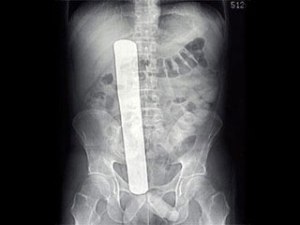

چند نکته راجع به جا ماندن لوازم جراحی در شکم بیمار

باندزیر خبر جا ماندن باند در شکم بیمار در یکی از بیمارستانهای ایران، کاربران بسیاری باز به جامعهء پزشکی فحاشی میکردند. زیر اون مطلب و در قالب یک کامنت طولانی سعی کردم خشم عمومی نسبت به جامعهء پزشکی را درک کنم (که تا حدی قابل درکه و تا حدی هم اغراق و بی انصافیه) و به عنوان عضوی از جامعهء پزشکی ایران، توضیحاتی رو در قالب ۷ نکتهء کوتاه بنویسم. عین اون کامنت را اینجا بازنویسی میکنم.

۳- به جا ماندن باند، گاز، پنبه و… درون بدن بیمار گوسیپیبوما میگن. میتونید لغت زیر را در گوگل سرچ کنید و ببینید تا چه حد همه جای دنیا وجود داره و فقط هنر پزشکان ایران نیست.

Gossypiboma

۴- یکی از روشهای الزامی و پیشنهاد شده برای جلوگیری از این اتفاق،‌ شمارش تک تک لوازم و مواد مورد استفاده قبل و بعد از جراحی است تا تیم جراحی بتونن مطمئن باشن چیزی گم نشده. ولی باید بدونید که در هر عمل جراحی بطور میانگین بین ۲۵۰-۳۰۰ عدد لوازم و وسایل جراحی استفاده میشه که در جراحی های بزرگتر تا ۶۰۰ قلم هم میرسه. به همین اصلا بعید نیست که دست آخر یکی از این تعداد از قلم بیوفته.

اما واقعیت اینه که برای جلوگیری و کنترل خونریزی درون شکم و برای تمیز نگه داشتن دید جراح، کلی باند و گاز استفاده میکنند و درون شکم جاسازی میکنند که همشون به دلیل جذب خون به رنگ درون شکم

در میان و گاهی تشخیص باند از بافت طبیعی بدن سخت میشه.

همونطور که گفتم یکی از راههای پیشگیری از این اتفاق شمردن تک تک لوازم و باند و گاز و… قبل و بعد از جراحیه که این کار برعهدهء پرستار یا دستیار جراح و پرسنل اتاق عمل است و جراح شخصا ممکنه آمار لوازم رو ندونه هرچند که در نهایت مسوول این اتفاق و سرپرست تیم جراحی خود جراح است.